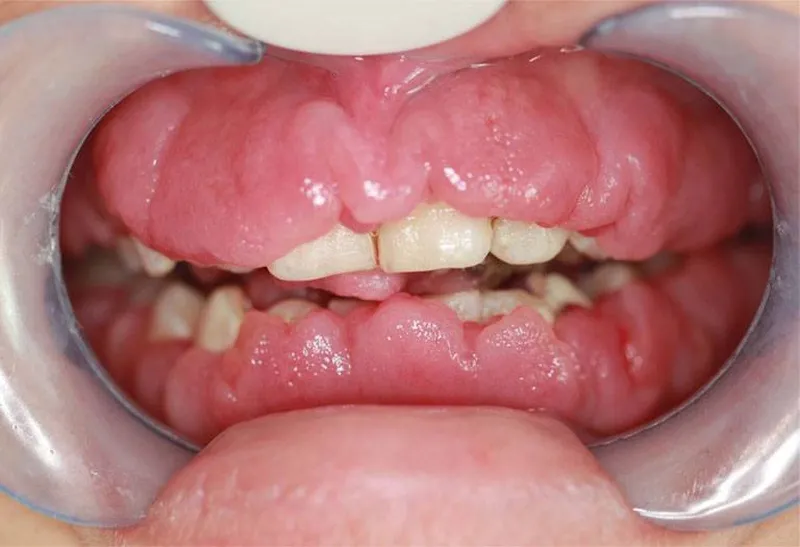

Viêm lợi phì đại là một tình trạng bệnh lý đặc trưng bởi sự tăng sinh quá mức của mô nướu. Từ đó dẫn đến hiện tượng nướu dày lên, sưng nề và có thể bao phủ một phần thân răng. Hiện tượng này thường là kết quả của phản ứng phì đại của mô lợi. Phản ứng này xảy ra đối với các tác nhân kích thích tại chỗ. Phổ biến nhất là mảng bám vi khuẩn còn mắc trong kẽ rằn. Đây là một yếu tố nguy cơ hàng đầu trong các bệnh lý nha chu.

Ngoài ra, tình trạng này cũng có thể phát sinh do tác dụng phụ của một số loại thuốc. Đặc biệt là các nhóm thuốc như thuốc chống động kinh (ví dụ: phenytoin). Ngoài ra là thuốc ức chế miễn dịch (cyclosporin), thuốc chẹn kênh canxi (như nifedipine). Tình trạng phì đại mô nướu không chỉ gây ảnh hưởng nghiêm trọng đến yếu tố thẩm mỹ. Điều này thể hiện qua việc nó làm cho răng trông ngắn hơn. Thậm chí khiến nướu chuyển sang màu đỏ đậm hoặc tím tái. Nó còn tác động tiêu cực đến chức năng sinh lý của khoang miệng.

Viêm lợi phì đại là tình trạng mô nướu tăng sinh bất thường. Hiện tượng này thường do phản ứng viêm kéo dài dưới tác động của mảng bám vi khuẩn. Ngoài ra là những ảnh hưởng của rối loạn nội tiết hoặc sử dụng thuốc. Các triệu chứng thường gặp bao gồm:

- Nướu bị phì đại rõ rệt, phồng lên quá mức so với bình thường. Màu sắc nướu chuyển từ hồng nhạt sang đỏ tươi hoặc tím thẫm. Điều này phản ánh tình trạng viêm cấp tính hoặc mạn tính.

Ở giai đoạn đầu, u xơ nướu có thể không gây triệu chứng đau đớn rõ rệt. Điều này khiến người bệnh và phụ huynh khó nhận biết. Tuy nhiên, nếu không điều trị sớm, mô nướu sẽ dần bao phủ thân răng. Từ đó gây cản trở nghiêm trọng đến chức năng ăn nhai, phát âm. Cùng với đó là vệ sinh răng miệng và cả sinh hoạt hàng ngày. Trong một số trường hợp nặng, can thiệp phẫu thuật nướu là cần thiết. Thông qua đó phục hồi chức năng và thẩm mỹ.